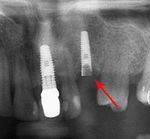

Screw fracture

Fracture of abutment screws (arrow) in 3 implants required removal of the remainder of the screw and replacement.